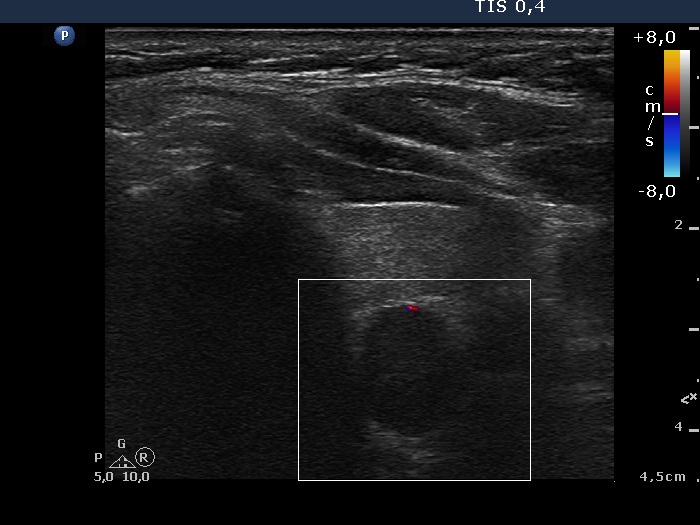

Right lobe, longitudinal scan

Middle part of the left lobe, transverse scan, color Doppler mode. This nodule is also avascular.